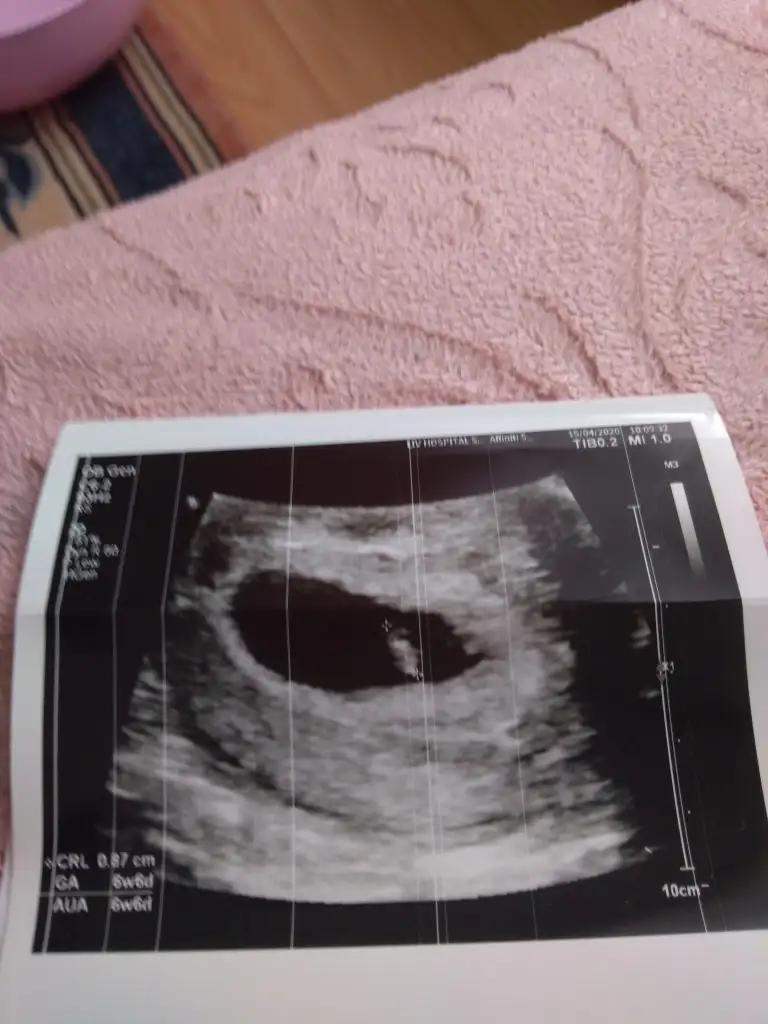

Kesenin şekline çevresine bebeğin kalp atış düzenine bakıp sağlıklı olduğuna karar veriyor doktorlar her hafta farklı sonuç öıkar zaten o yüzden arayı açın 3 4 haftada bir gidin doktora ben önceki hamileliğimde her hafta gidiyordum riskli gruptayım diye her hafta farklı çıkıyordu insanı strese sokuyor bu durum

Kizlar nasil sizce

Eklentiler

• 15869434648452505333207605459813.webp

15869434648452505333207605459813.webp

30,3 KB · Görüntüleme: 66